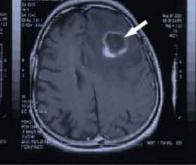

Pour combattre le glioblastome, un redoutable cancer du cerveau qui résiste à la chimiothérapie, une équipe internationale de recherche a développé un nouveau vaccin thérapeutique.

Un malade anglais de 63 ans, Robert Demeger, est le premier patient en Europe à avoir bénéficié de cette nouvelle thérapie, dans le cadre d’essais cliniques de phase 3 portant sur 300 patients.

Les études préliminaires menées aux États-Unis sur cette approche, baptisée DCVax-brain therapy, ont montré qu’elle pouvait doubler la survie des patients atteints de ce type de tumeur du cerveau.